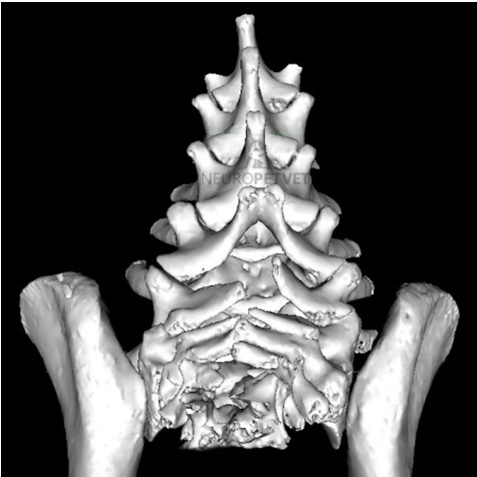

Η αξονική τομογραφία (CT) παρέχει εξαιρετική λεπτομέρεια της οστικής αρχιτεκτονικής και βοηθά στον χαρακτηρισμό των σπονδυλικών δυσμορφιών.

Τρισδιάστατη ανασύνθεση από CT (νευροτόμια Ο3 – ιερό) νεαρού English Bulldog με δισχιδή ράχη. Σημειώστε την ατελή σύγκλειση των ακανθωδών αποφύσεων των Ο6, Ο7 και του ιερού.